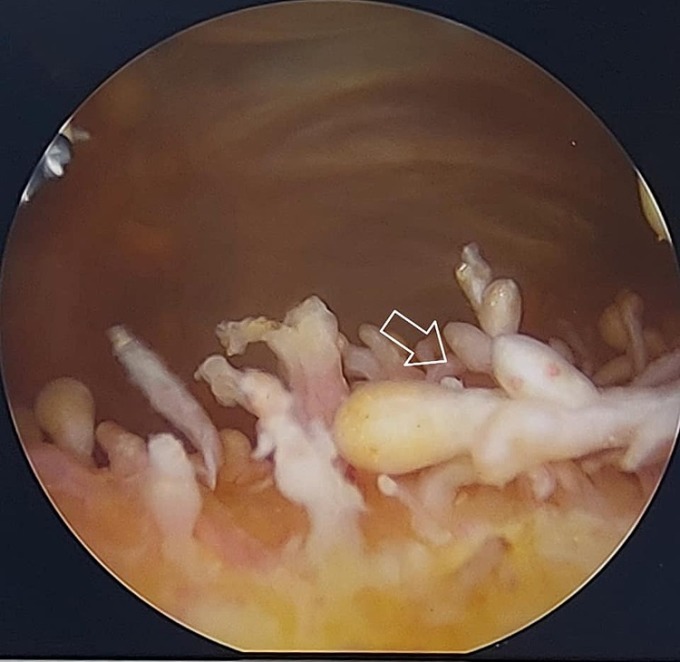

Old  Arrow Hình ảnh 'cánh đồng nấm' của bệnh viêm khớp gối thời gian dài

Bệnh nhân 63 tuổi viêm màng hoạt dịch khớp gối quá lâu khiến màng hoạt dịch tua rua hiếm gặp, bác sĩ nội soi nhìn thấy hình ảnh như "cánh đồng nấm".

Bác sĩ Hiền chỉ định nội soi khớp gối bệnh nhân, kết quả hình ảnh là niêm mạc hoạt dịch trong khớp gối tua rua, chỗ đỏ rực, chỗ lại trắng, cái to cái nhỏ, như cánh đồng nấm. Khi nhìn thấy hình ảnh nội soi viêm khớp gối của bệnh nhân, anh rất bất ngờ liền chia sẻ lại với đồng nghiệp.

Bác sĩ cho biết bình thường màng hoạt dịch tại khớp gối nhẵn bóng. Khi viêm khớp lâu ngày, màng hoạt dịch rất dày, các nhung mao màng hoạt dịch gần như mắt thường nhìn sẽ phẳng lỳ, kể cả khi nội soi, phóng đại đến 4 lần "cũng không bao giờ thấy hình ảnh nào đặc biệt như thế".

Một vài đồng nghiệp của bác sĩ Hiền sau đó đăng tải ảnh "viêm khớp như cánh đồng nấm" lên mạng xã hội nhận được nhiều lượt like và chia sẻ. Nhiều người còn ví hình ảnh như đông trùng hạ thảo trong khớp gối bệnh nhân.

Hình ảnh niêm mạc màng hoạt dịch trong khớp gối bệnh nhân giống như một cánh rừng nấm. Ảnh: Bác sĩ cung cấp

Bác sĩ Hiền cho biết, khớp của bệnh nhân này tràn dịch nhiều, đầu gối biến dạng sưng to, màng dịch dày, kết quả chụp, chiếu, xét nghiệm thấy tăng axit uric trong máu, thoái hóa khớp độ 3, viêm dày màng dịch, các sụn của khớp có chỗ bị bong tróc. Bác sĩ chẩn đoán viêm màng hoạt dịch khớp gối. Đây là tình trạng viêm túi chứa dịch lỏng ở khớp gối. Màng hoạt dịch giúp giảm ma sát và là miếng đệm chịu lực giữa hai đầu xương và gân, cơ, da gần khớp.

Ê kíp mở nội soi chọc hút ra nhiều dịch màu nâu đen, sau đó rửa khớp sạch sẽ, nhìn thấy màng dịch dày, tua rua như cánh đồng nấm liền cắt sạch màng dịch, tái tạo sụn. Sau phẫu thuật, bệnh nhân sức khỏe ổn định, ngủ ngon.